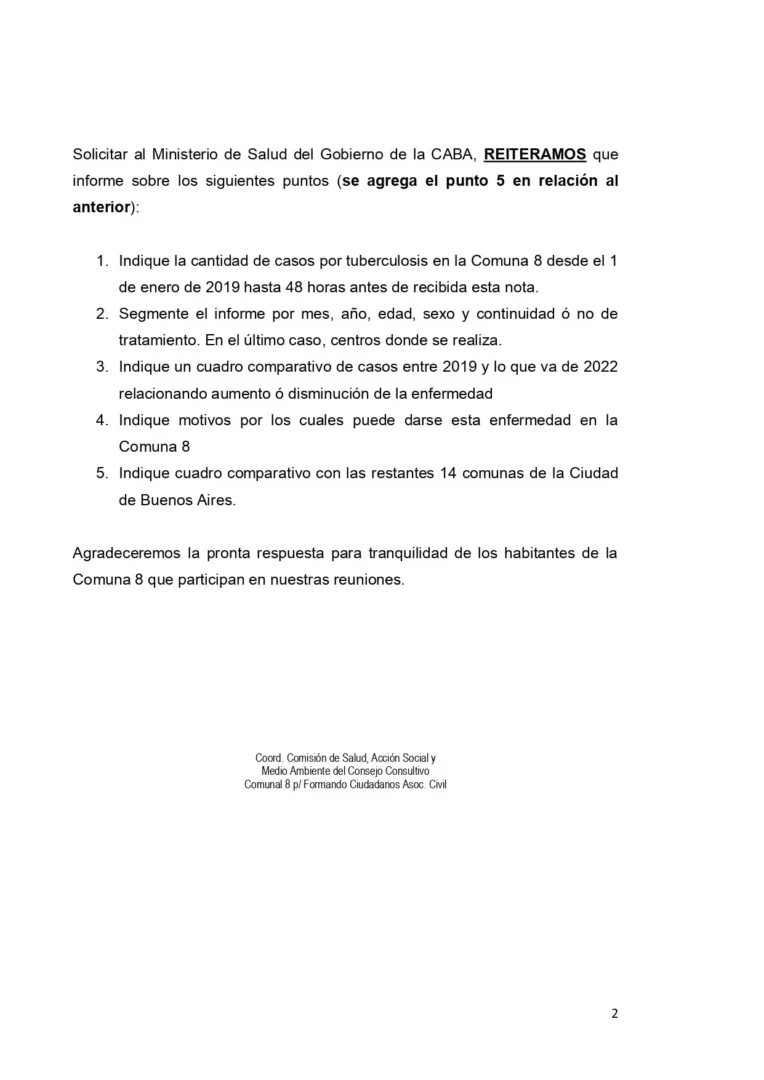

Es una enfermedad contagiosa que desde hace muchos años se encuentra en nuestra Comuna 8 y en el sur de la Ciudad

Hace tiempo que no recibimos el informe “segmentado” de cada Comuna por lo tanto, nos vemos en la necesidad de solicitar una vez más, un pedido de informes

En este caso, lo que hacemos es reiterar uno que ya hicimos este año y no respondieron nada